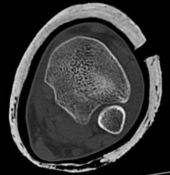

Tibial shaft fracture extending into the plafond—plate fixation Case description A 26-year-old man fell from …

Tibial shaft fracture extending into the plafond—intramedullary fixation Case description a A 25-year-old wom…